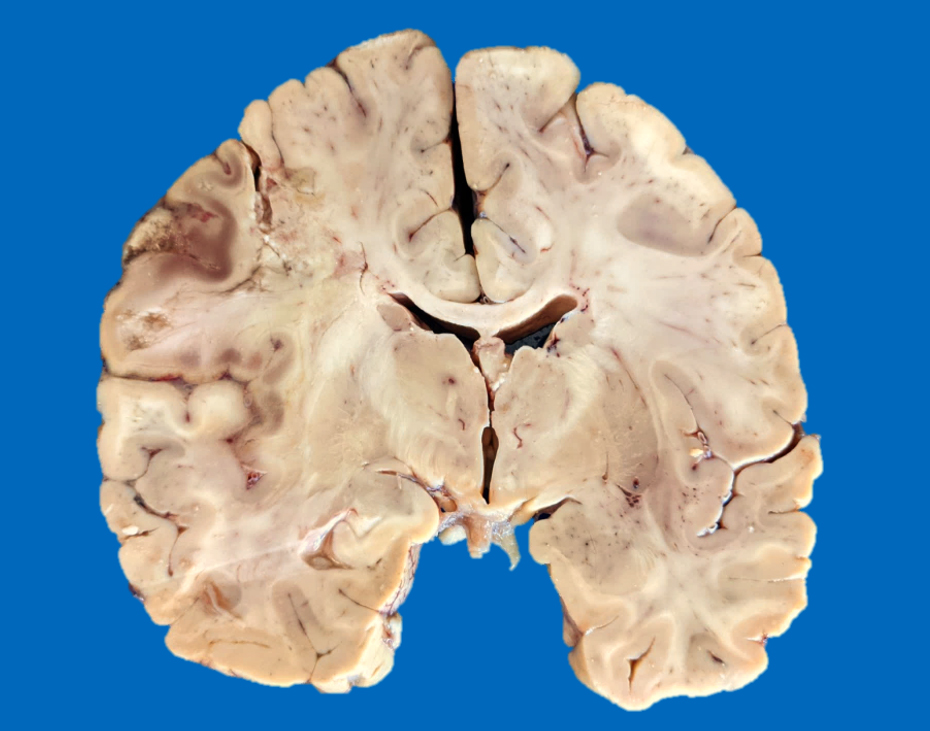

Gross description

- Time between stroke and death is a major determinant of the gross features

- Completely accurate dating of an infarct based on the gross features is not possible, especially cavitated lesions

- < 8 hours to 48 hours

- Undetectable if the infarct occurred < 8 hours before death

- Congestion of gray matter and edema (Histopathology 2011;58:333)

- Dusky discoloration and blurring of the gray-white matter junction

- Ill demarcated borders

- Reperfusion of an ischemic lesion where vessels are also affected can become hemorrhagic (Stroke 1986;17:586)

- Hemorrhagic discoloration can be limited to a specific vascular territory

- Commonly observed as secondary infarcts in the setting of brain herniations (e.g., obstruction of pericallosal artery in subfalcine herniation, obstruction of posterior cerebral artery in uncal herniation)

- 2 days to a few months (Histopathology 2011;58:333)

- Marked tissue softening

- Cracking artifact: demarcates the necrotic area

- Tissue edema (e.g., midline shift, narrowing of the sulci, convexity flattening)

- Dusky discoloration and blurring of gray-white matter junction

- Cerebellar infarcts show effacement of the folia

- Chronic (months - years)

- Cavitation (i.e., cystic infarct)

- Thin cortical remnant overlying the cavitation

- In long term survivors of severe global hypoxic ischemic encephalopathy, a markedly thin cortex can be observed due to laminar necrosis

- Lateral ventricle asymmetry can be seen (i.e., ex vacuo ventricular dilation of the affected hemisphere)

- Anterograde loss white matter volume due to an ischemic insult (e.g., atrophy of the ipsilateral cerebral peduncle and pyramid after an MCA infarct with degeneration of the corticospinal tract), ipsilateral brainstem atrophy after extensive supratentorial stroke (corticospinal tract and frontopontine fiber degeneration) and subsequent contralateral cerebellar atrophy due to transsynaptic degeneration (AJNR Am J Neuroradiol 2008;29:354, Eur Radiol 2006;16:592)

- Postinfarct anterograde white matter loss of volume occurs due to Wallerian degeneration or transsynaptic degeneration (AJR Am J Roentgenol 1998;171:813)

- Lacunar infarct: arbitrarily defined as cystic infarcts < 10 mm in length

- Predominantly found at basal ganglia, internal capsule, pons

- Binswanger disease

- White matter structures, including corpus callosum, corona radiata, internal capsule and anterior commissure shows marked loss of volume, discoloration, softening and granular texture predominating in the periventricular areas (Neurology 1995;45:626, J Neurol Sci 2010;299:9)

- Lacunar or large infarcts are frequently observed

- Cerebellar white matter is also commonly affected

- Associated with vascular dementia

Gross images